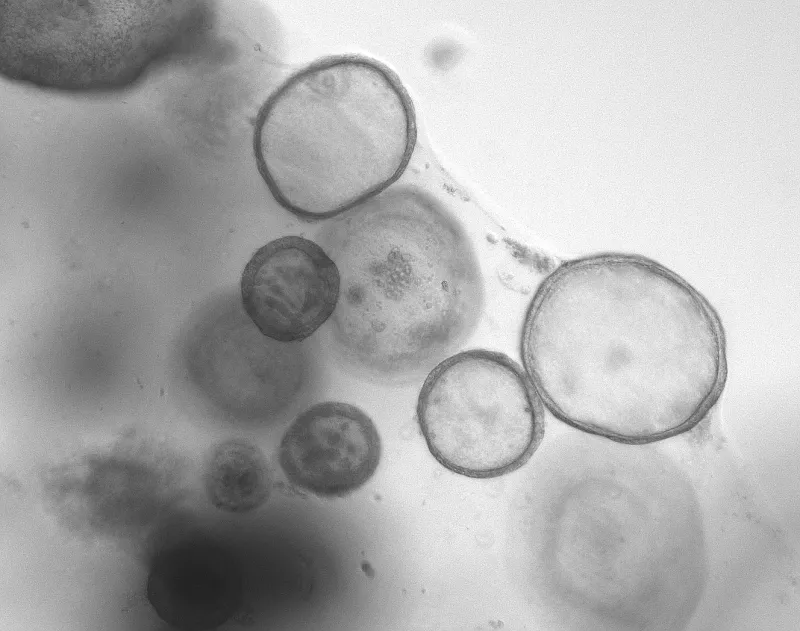

Grey microscopic image of Human Intestinal Organoid cells.

Human Intestinal Organoid modeling of bariatric surgery.

Cells of the small intestine microscopic image size 100 times actual size.